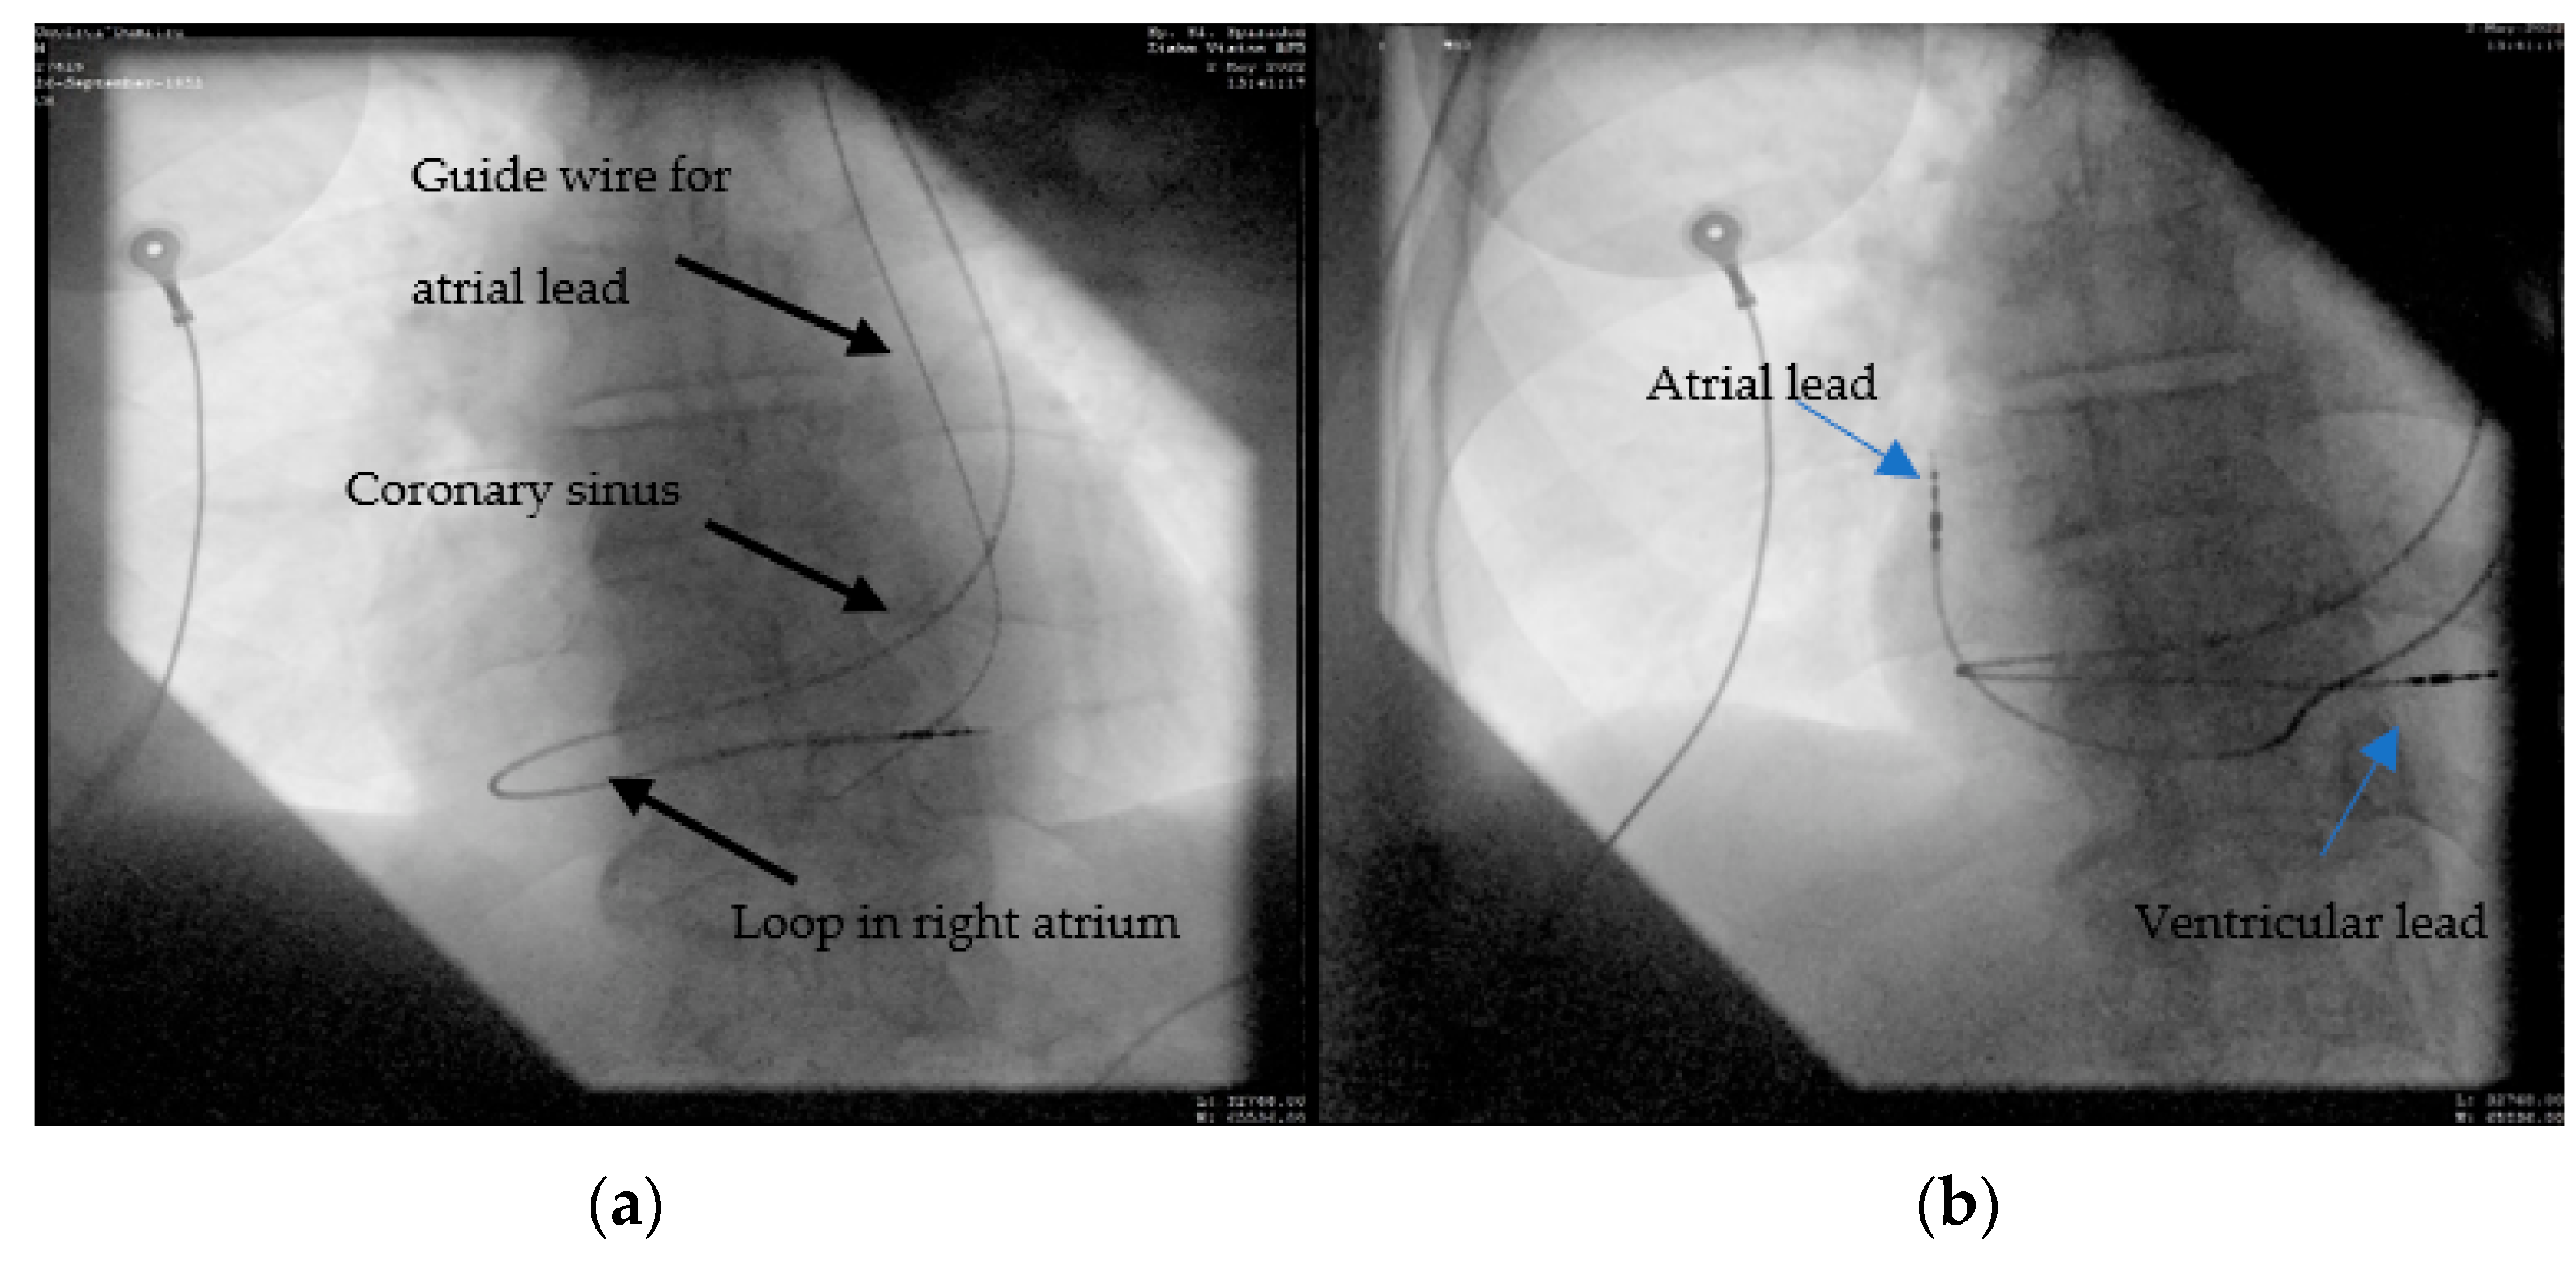

2.4. Case 4. (Type IIIB)